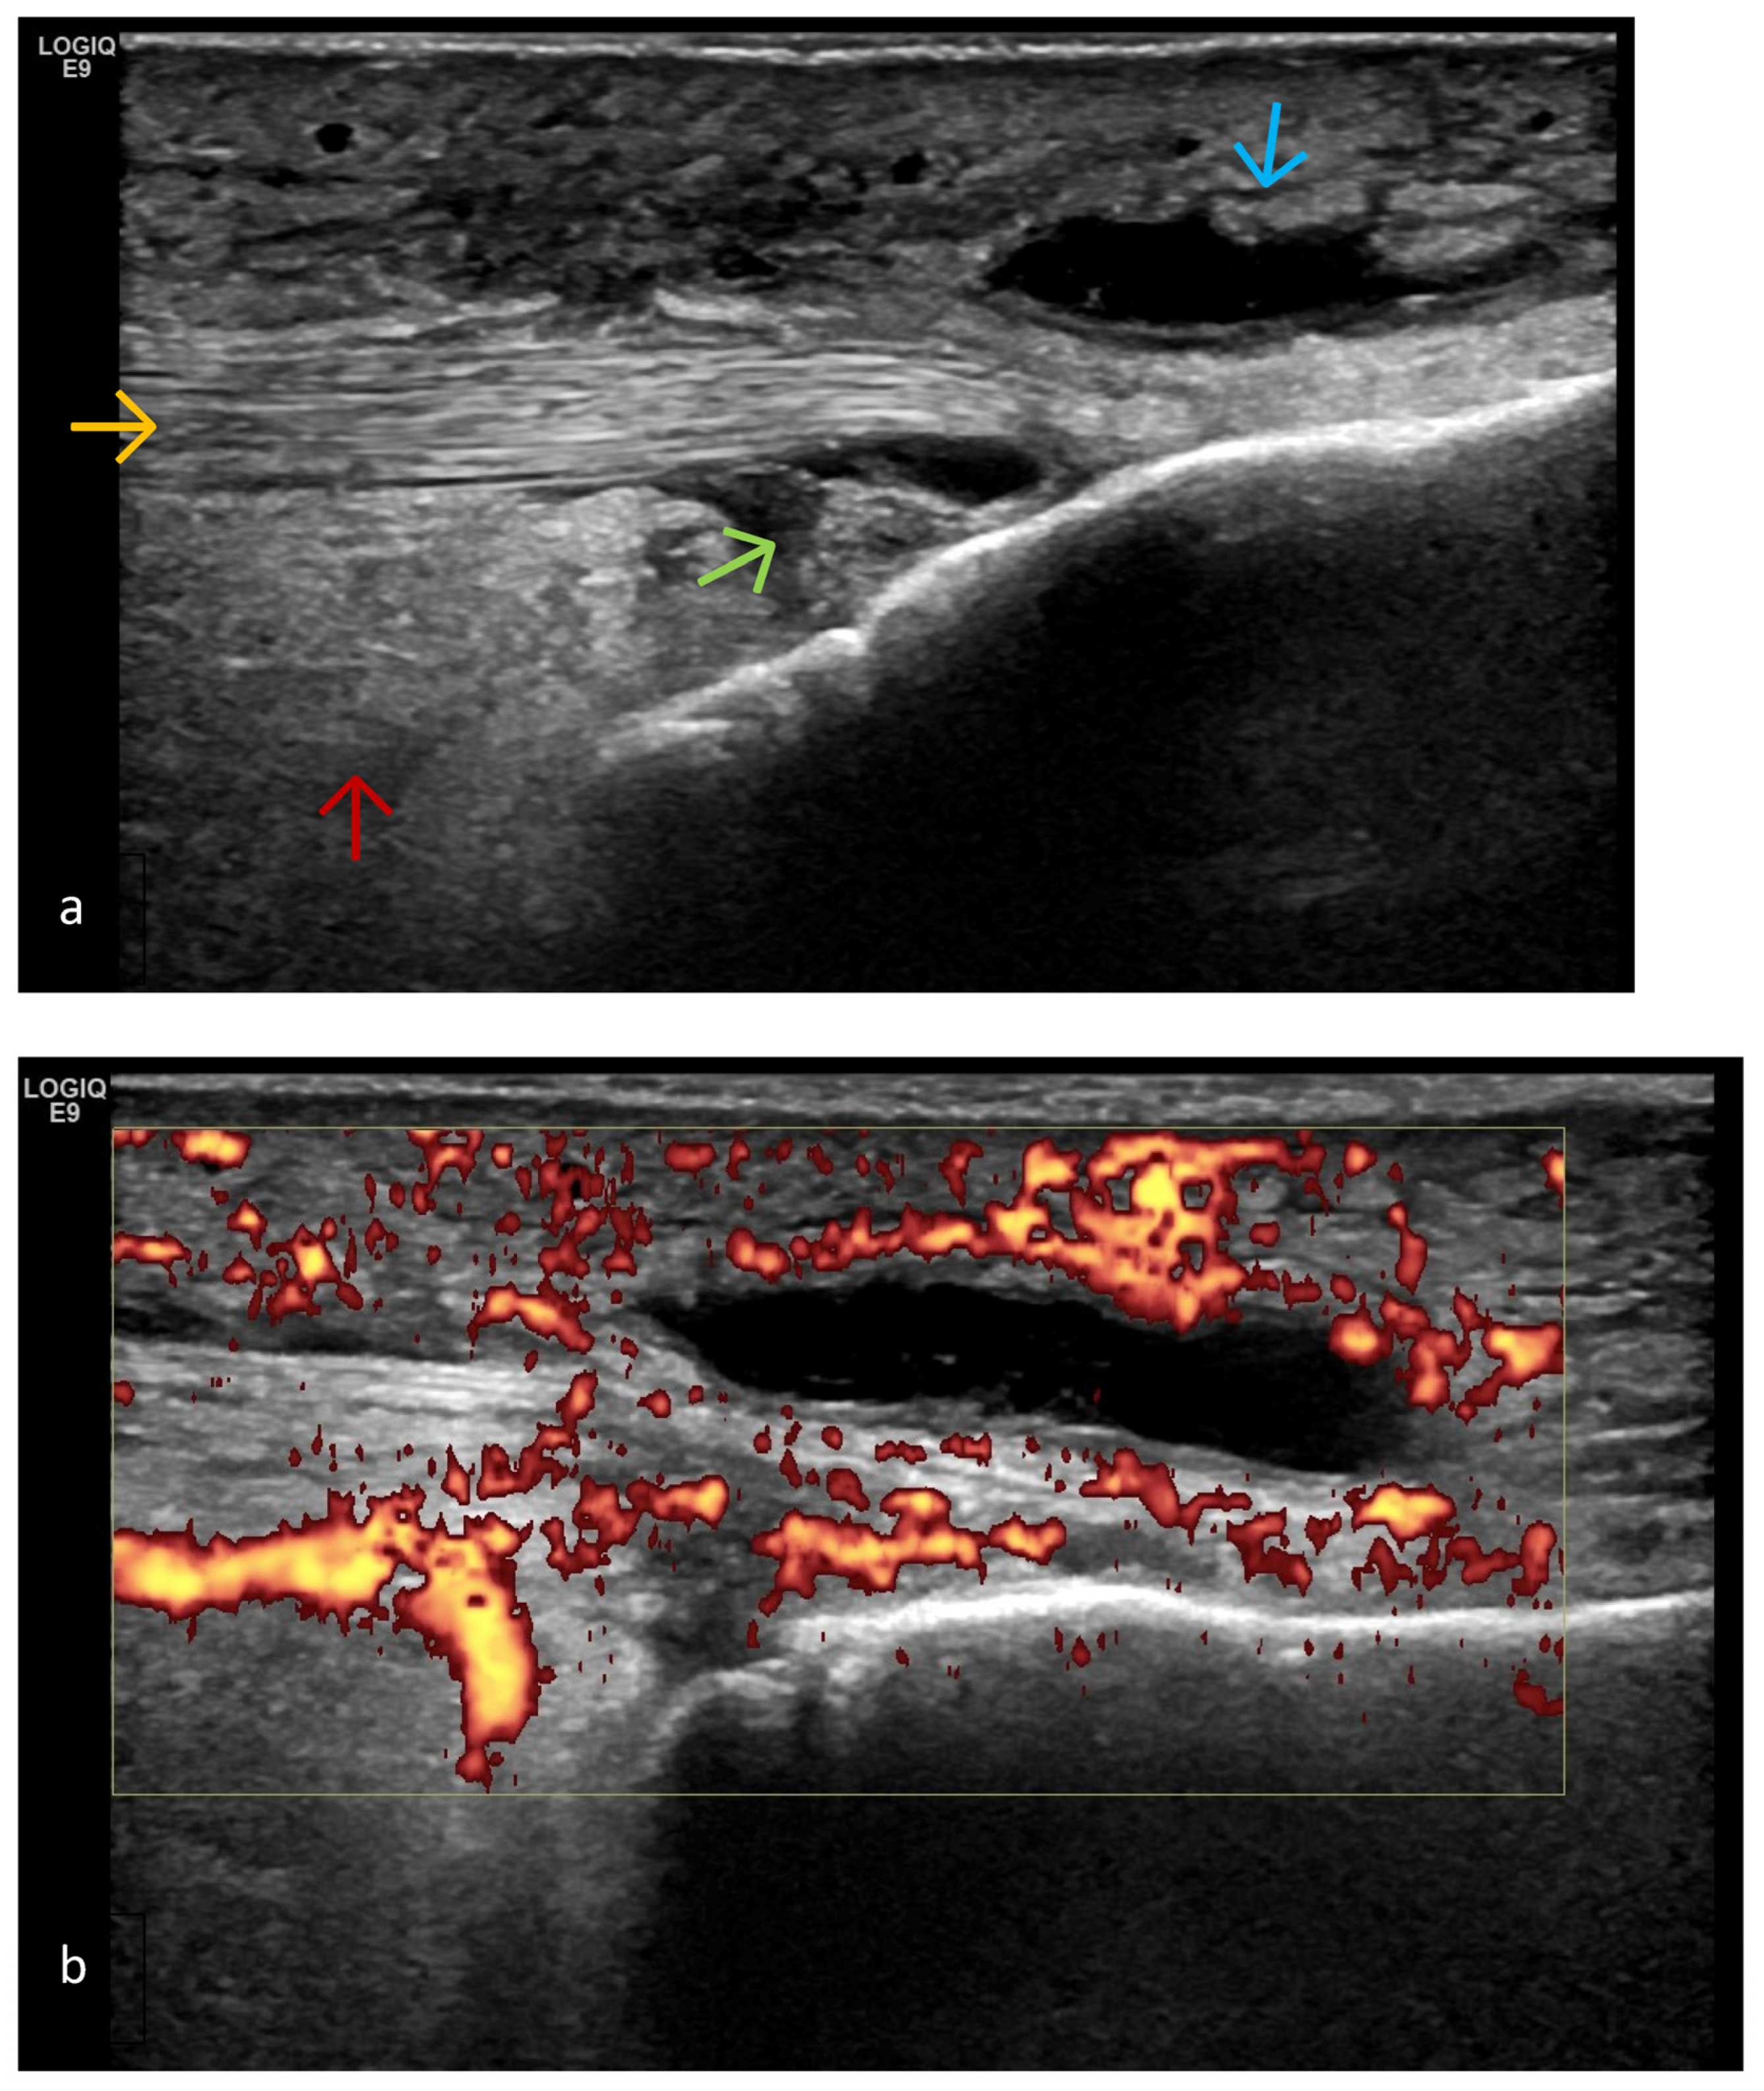

- Predominant cartilage destruction (with almost no synovitis and intra-articular effusion);

- Altered subchondral bone (superficial bone erosions or osteophytes);

- Changes in extra-articular soft tissue (ligaments, tendons, capsule, entheses, muscles, bursae, Baker’s cysts, menisci—for knee joints); periarticular cystic lesions (including meniscal);